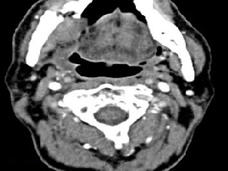

Study Explores Jaw Problem Linked to Zoledronic Acid, Finds Risk Factors

A recent study quantified the risk of osteonecrosis of the jaw for patients who take zoledronic acid to manage complications from cancer that has spread to the bone. The study also examined risk factors for osteonecrosis of the jaw in these patients.